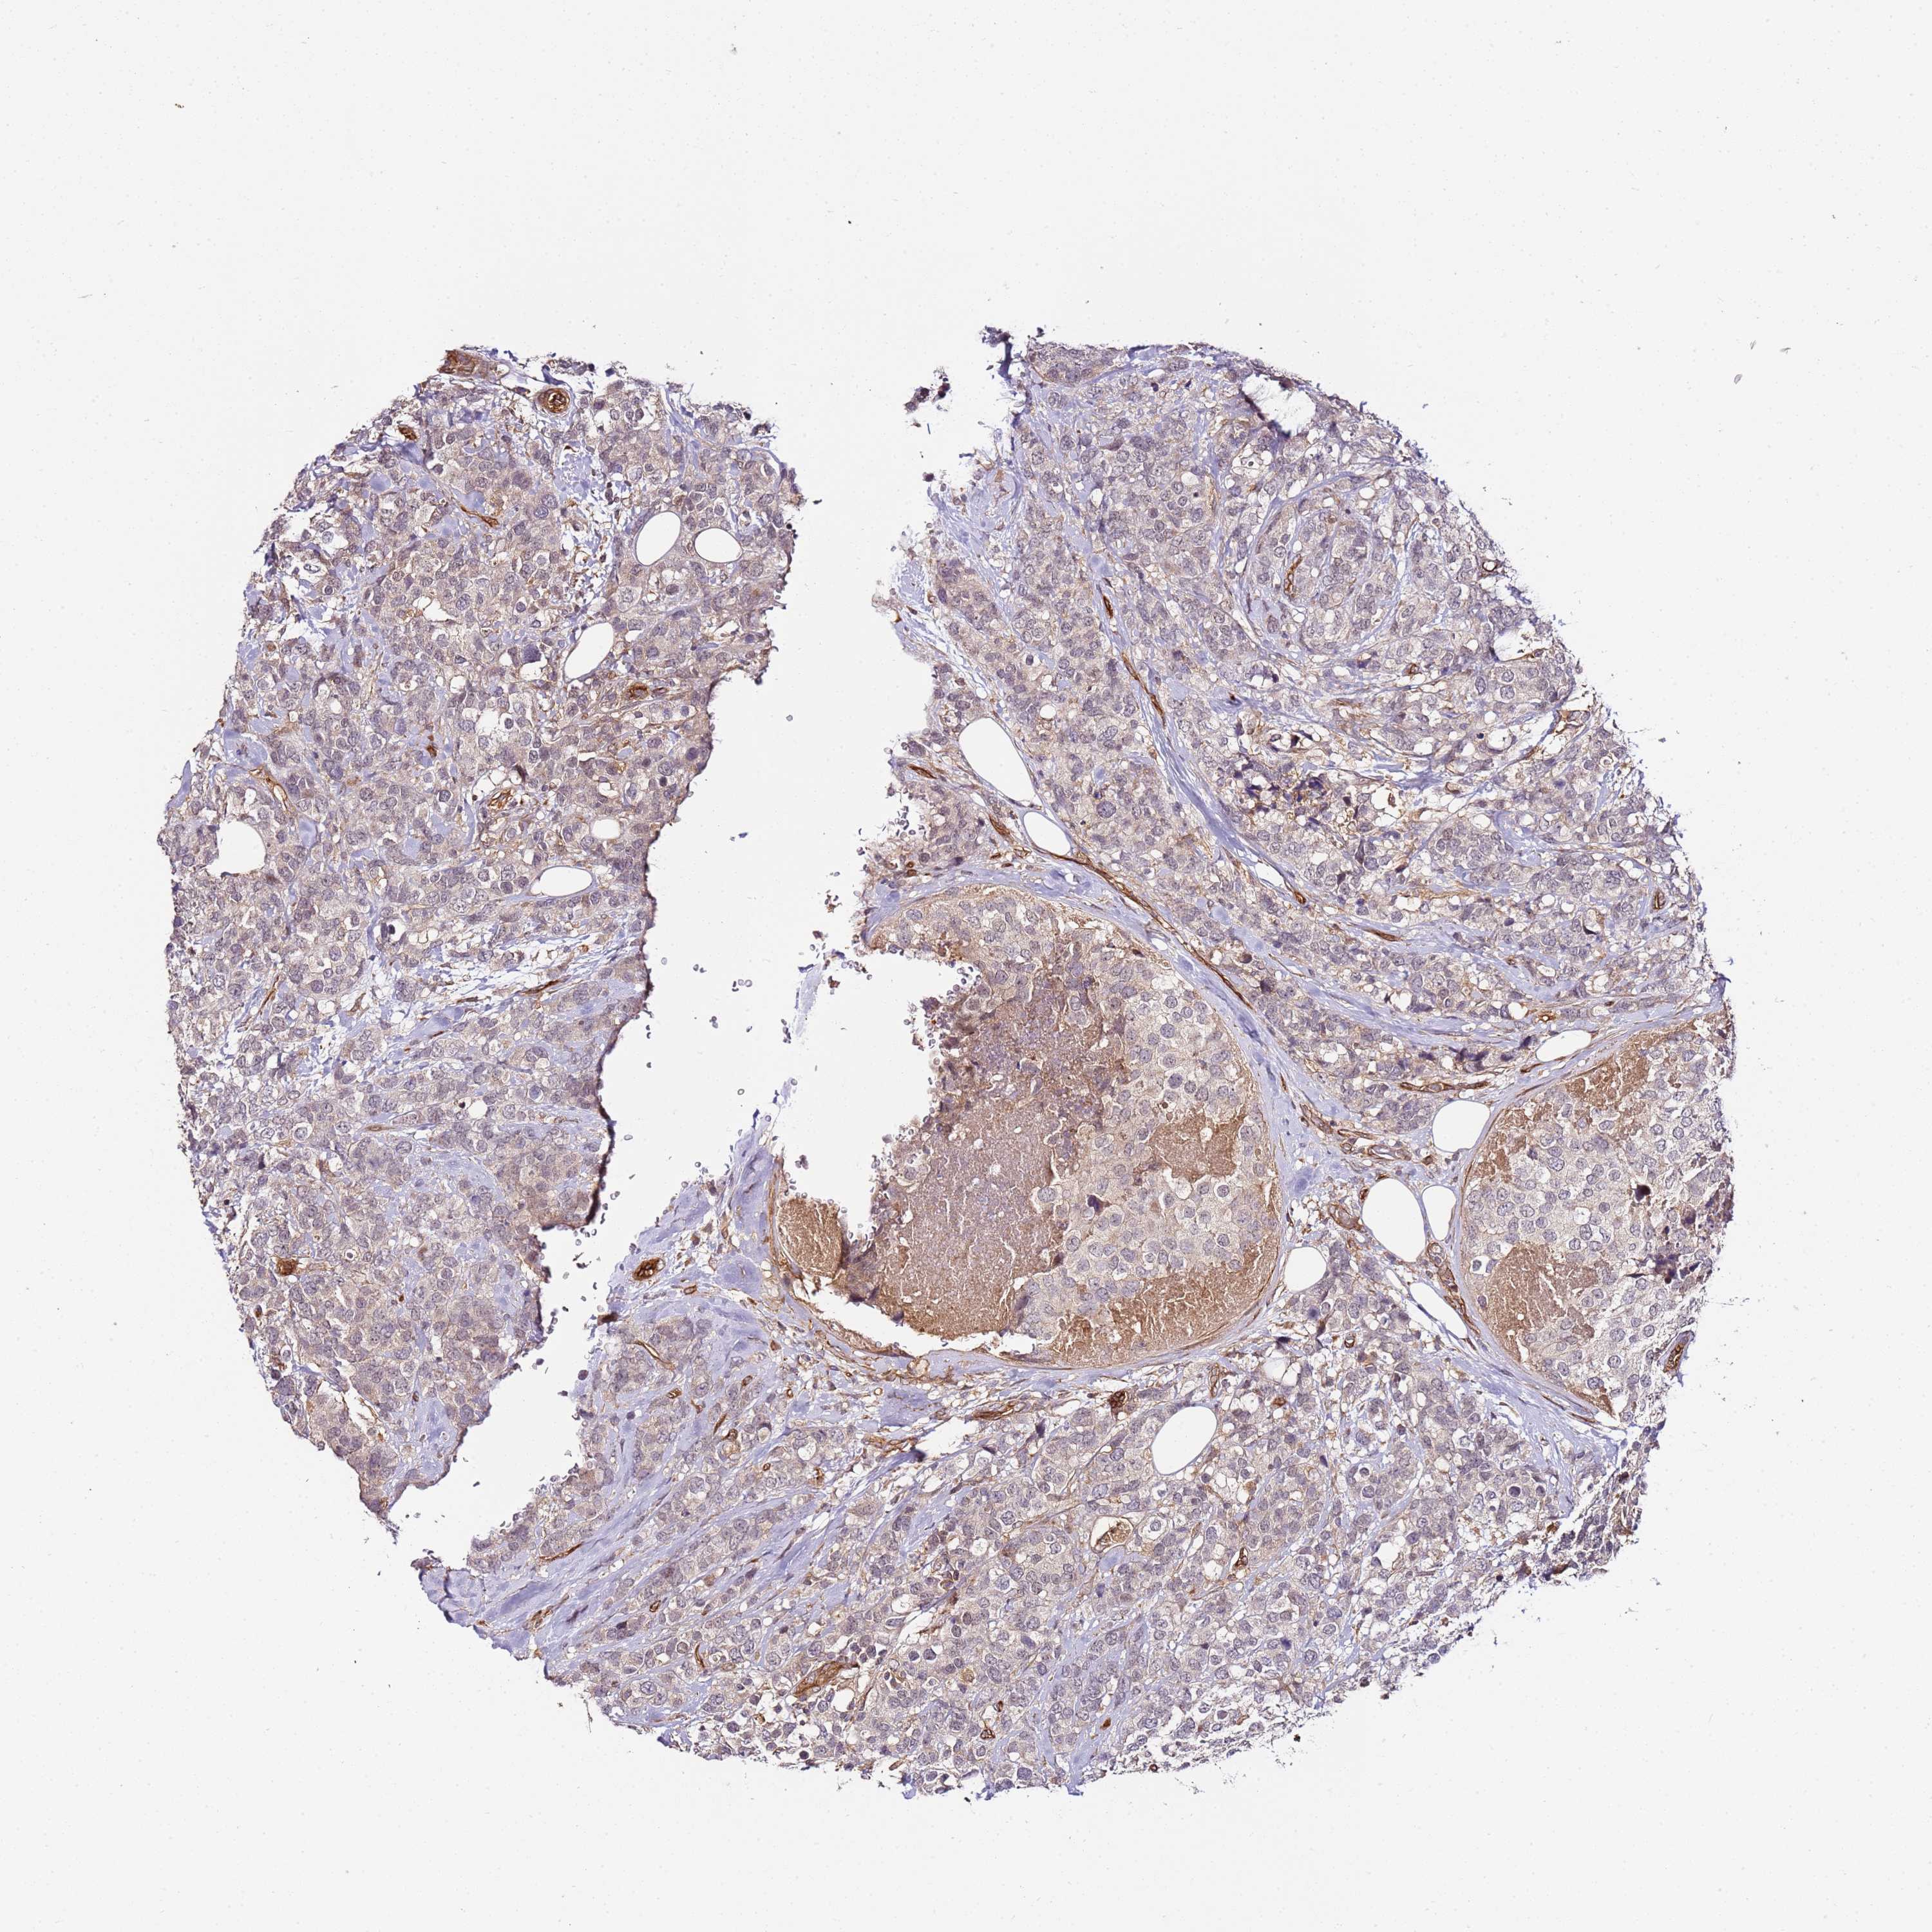

CANCER BREAST CANCER Show tissue menu

BRCA TCGA BRCA VALIDATION PROTEIN EXPRESSION